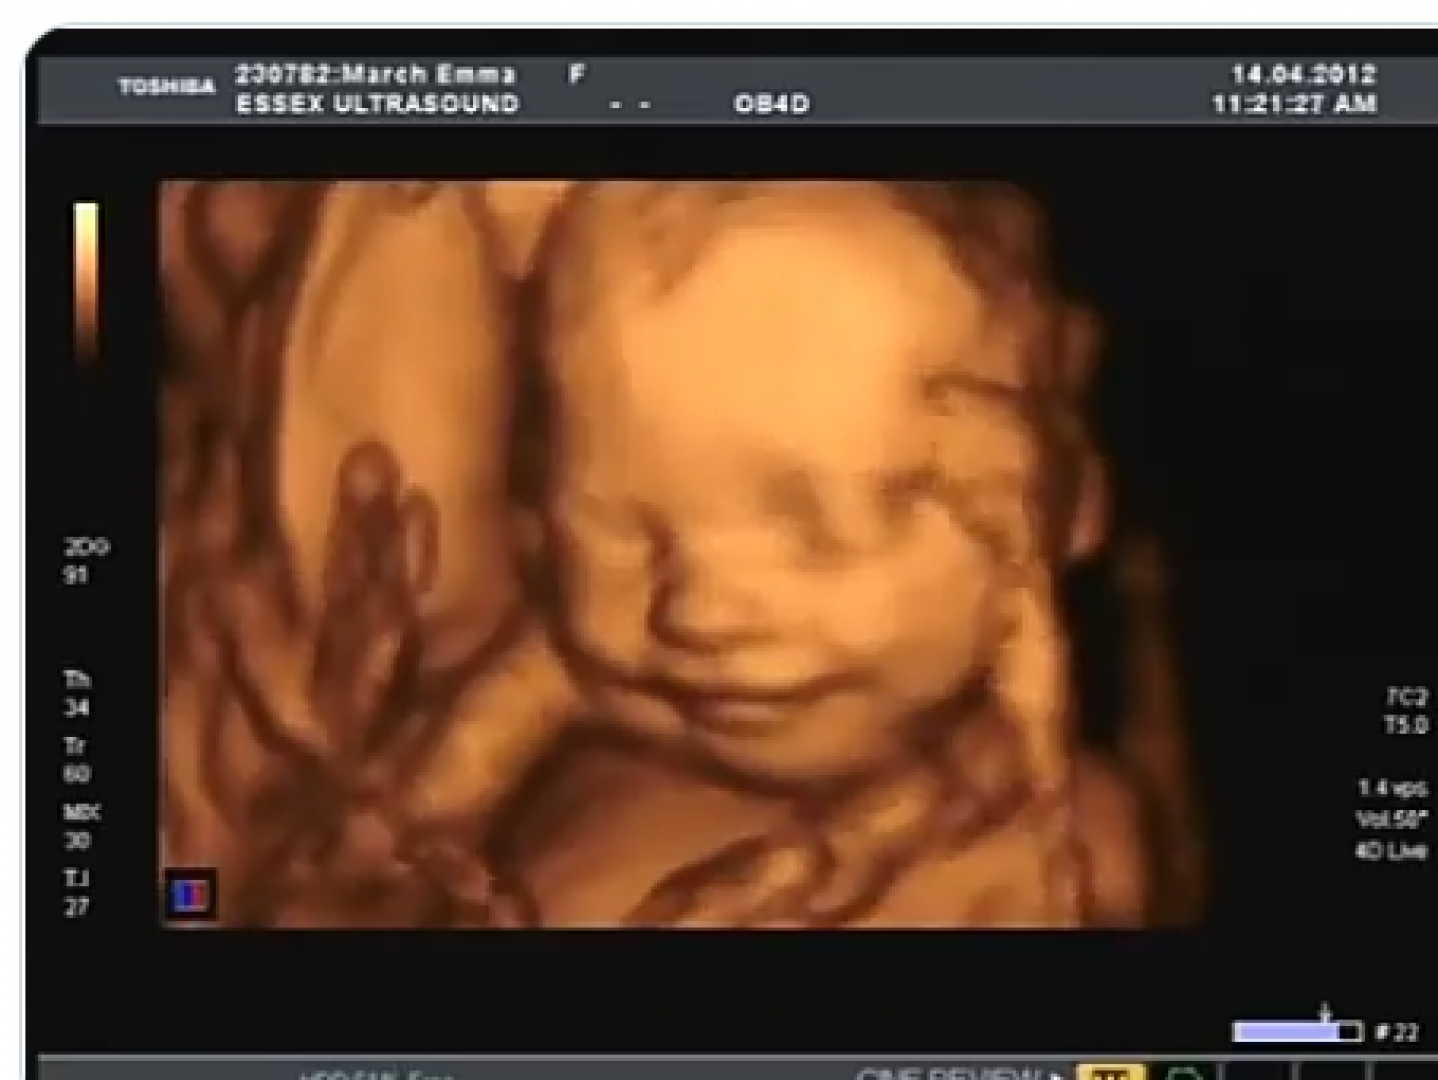

- بالرغم من صغر حجم قلب الجنين في هذه المرحلة، فإنه ينبض بشكل مستمر ويتحرك لضمان تدفق الدم إلى كل أجزاء الجسم، ويتم قياسه باستخدام جهاز فحص الأشعة فوق الصوتية.

- يجب أن يتم هذا الفحص خلال زيارات الحمل المستمرة في هذه المرحلة، ويتم حتى الآن تحديد المعدل الطبيعي لنبضات الجنين الذي يجب أن يكون بين 120 -170نبضة في الدقيقة.

- بداية من الأسبوع السادس حتى الأسبوع التاسع، تستطيع الأم فحص طفلها للتأكد من سلامته عن طريق التصوير الإشعاعي والموجات الصوتية للاطمئنان على نبض الجنين.